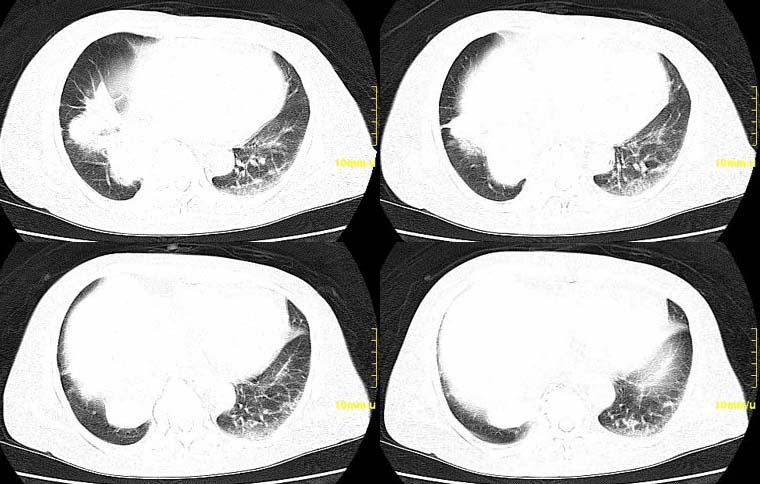

请大家讨论右下肺占位性质。ct值约35-55hu

右肺门后侧环绕支气管的软组织肿块,内见点状钙化,远端有阻塞性炎症,年龄76,ct值约35-55hu ,考虑右肺中心型肺癌。建议支气管镜鉴。

右下肺,右肺门后方见团块状软组织密度影,边缘呈分叶状,其内见斑点状钙化,肿块内部支气管腔闭塞。肿块后方可见胸膜尾征,外侧方见斑片状模糊阴影。右肺门淋巴结增大。

考虑:右侧中央型肺癌伴阻塞性肺炎及右肺门淋巴结转移